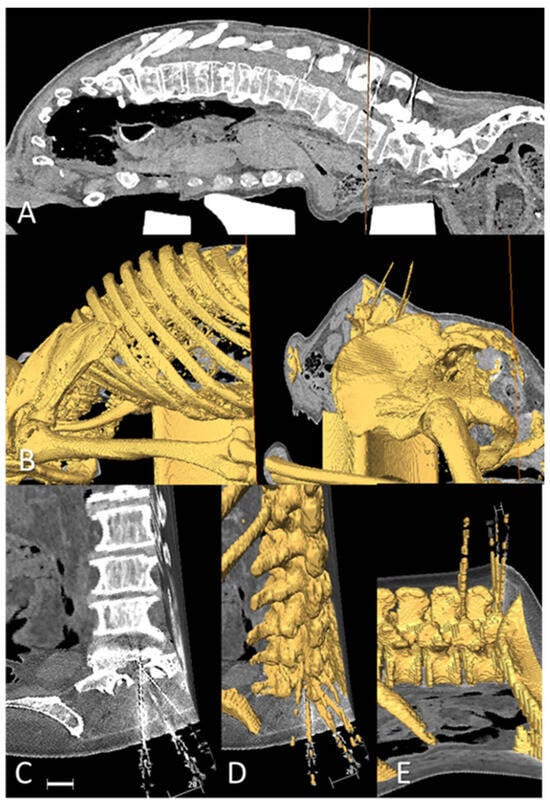

2.5. CT and 3D Reconstruction

2.6. Anatomical Illustration of Needle Path and Affected Structures

3. Results